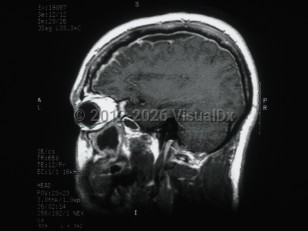

Vomiting, Headache, 50-59 year old Female

Subarachnoid hemorrhageSubarachnoid hemorrhage

Cerebral edemaCerebral edema

Hydrocephalus

Idiopathic intracranial hypertensionIdiopathic intracranial hypertension

Epidural intracranial hematomaEpidural intracranial hematoma

PapilledemaPapilledema

Subdural hematoma

Brain abscessBrain abscess

Posterior fossa hematoma

MeningiomaMeningioma

Pituitary tumor

Subdural empyemaSubdural empyema

CraniopharyngiomaCraniopharyngioma